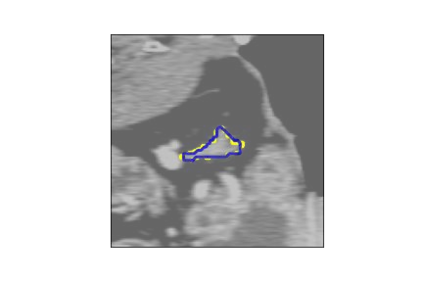

The human annotations are imperfect, especially when produced by junior practitioners. Multi-expert consensus is usually regarded as golden standard, while this annotation protocol is too expensive to implement in many real-world projects. In this study, we propose a method to refine human annotation, named Neural Annotation Refinement (NeAR). It is based on a learnable implicit function, which decodes a latent vector into represented shape. By integrating the appearance as an input of implicit functions, the appearance-aware NeAR fixes the annotation artefacts. Our method is demonstrated on the application of adrenal gland analysis. We first show that the NeAR can repair distorted golden standards on a public adrenal gland segmentation dataset. Besides, we develop a new Adrenal gLand ANalysis (ALAN) dataset with the proposed NeAR, where each case consists of a 3D shape of adrenal gland and its diagnosis label (normal vs. abnormal) assigned by experts. We show that models trained on the shapes repaired by the NeAR can diagnose adrenal glands better than the original ones. The ALAN dataset will be open-source, with 1,594 shapes for adrenal gland diagnosis, which serves as a new benchmark for medical shape analysis. Code and dataset are available at https://github.com/M3DV/NeAR.